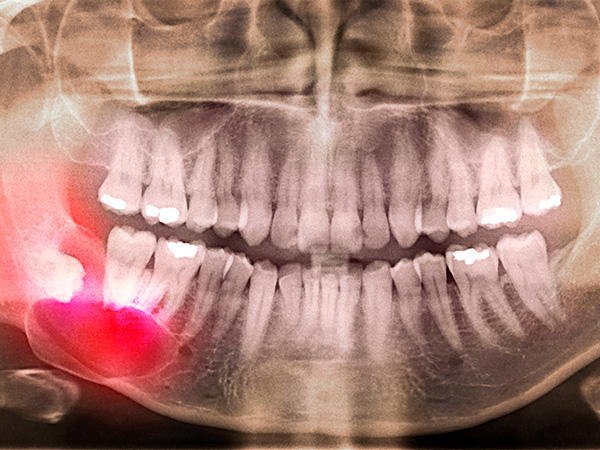

사랑니가 신경과 맞닿아 있는 상황을 제외하고는 안전하고 신속하게 발치가 가능합니다.

사랑니가 비스듬하게 누워있는 경우에는 수술적인 방법을 통해 발치를 해야 하며 신경과 맞닿아 있는 경우에는 사랑니 발치 시 신경손상의 우려가 있음으로 주의하셔야 합니다.

방사선 검사를 통해 사랑니 위치와 신경과의 거리를 먼저 확인한 뒤, 가능한 경우에 한해 당일 발치를 도와 드려 갑작스러운 통증으로 인한 불편을 빠르게 줄이는 데 도움을 드립니다.

사랑니 뿌리근처에는 아래턱 신경이라는 커다란 신경이 지나갑니다. 개개인마다 다르지만 뽑는 과정에서 신경에 손상을 일으킬 가능성이 있습니다. 신경손상 가능성에 대한 사전 분석이 필요하며 손상가능성이 있다고 판단되는 경우 경험 많은 의사에게 조심스러운 발치 및 후처리가 요구됩니다.